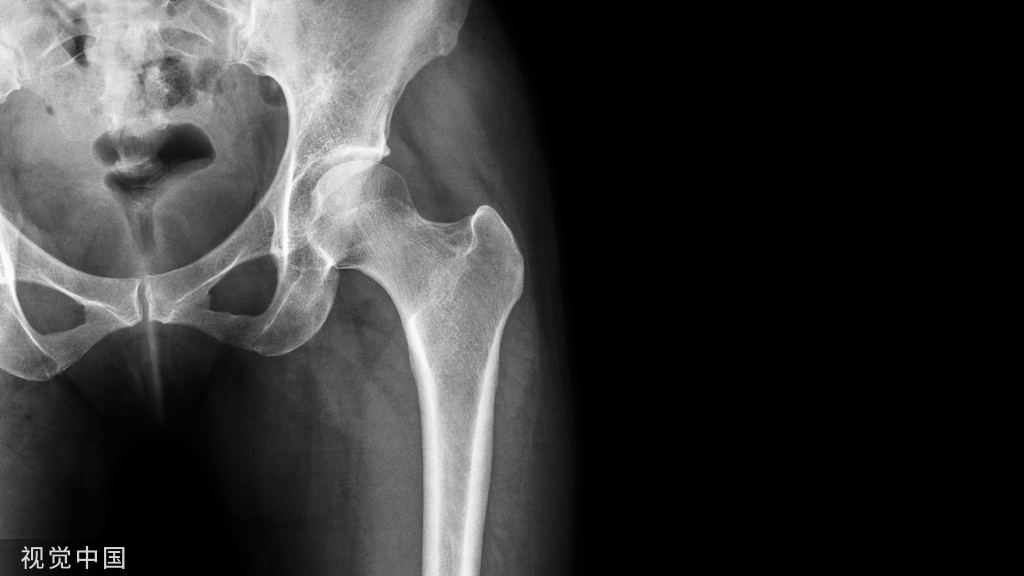

前路骨盆内固定术的入路技巧!

• 沿皮纹行普芬南施蒂尔(Pfannenstiel)切口,耻骨联合上1~2cm,长约15cm。